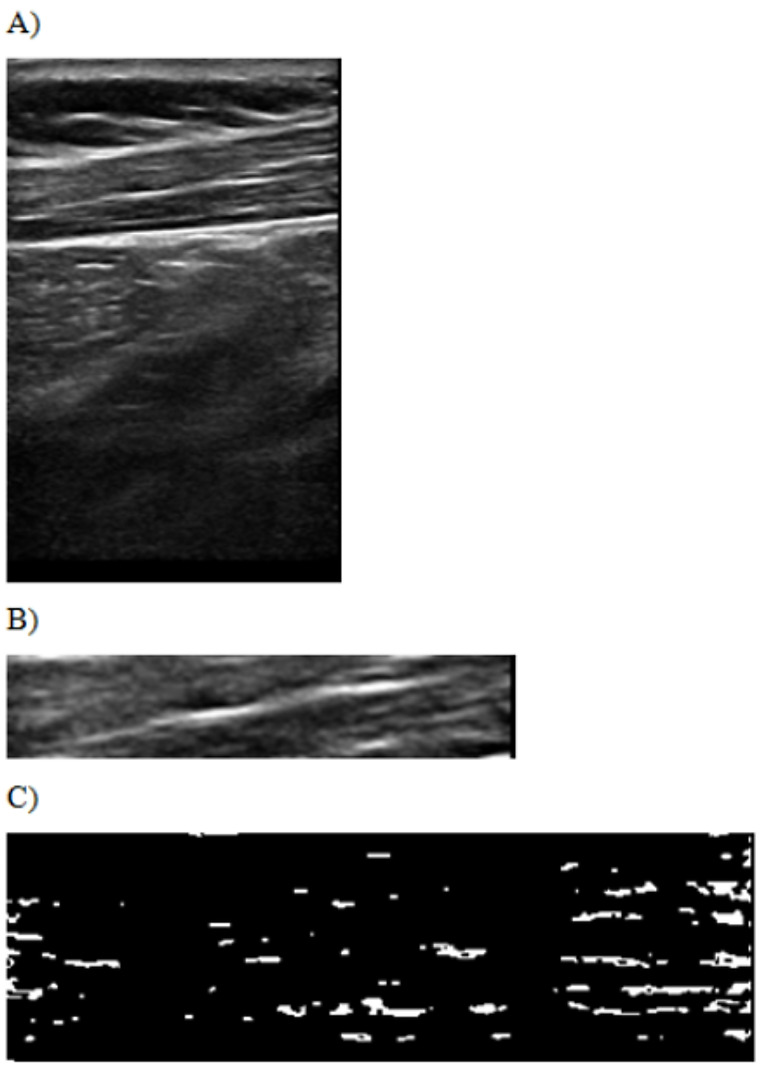

Initially, the ROI images were thresholded using MATLAB 2016b software. Thresholding involves converting the grayscale of the original image into a binary scale. Grayscale values below the predetermined threshold were assigned a value of 0, whereas values above the threshold were assigned a value of 1. This process created a binary “image” system where areas with a value of 1 represented blobs, defined as spatially connected regions of pixels with similar echointensity values. Blobs were identified in regions within the 95th and 99th percentiles of echointensity values that exceeded the threshold (Fig. 2).

Fig. 2.

B-mode ultrasound image of the upper trapezius muscle (A). The region of interest (ROI) area of the upper trapezius muscle (B). Blob positions within the ROI after thresholding (C)